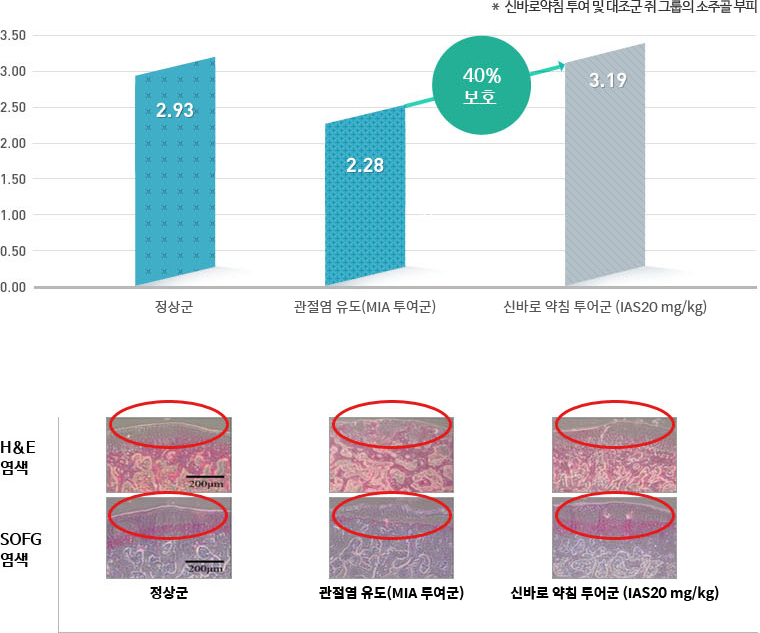

손상된 뼈·연골 보호 및 정상 회복

골관절염을 유발시킨 쥐의 관절에 신바로약침을 투여한 결과, 뼈를 구성하는 요소 중 하나인

소주골의 부피가 위약을

투여한 그룹에 비해 40% 보호됐습니다.

투여한 그룹에 비해 40% 보호됐습니다.

- 연구기관 : 서울대학교 천연물과학연구소 연구팀

- 저널명 : '차이니즈 메디신' (미국 보완대체의학 분야 SCI급 국제 학술저널) 2016년 5월호

- 논문명 : Effects of intra-articular SHINBARO treatment on monosodium iodoacetate-induced osteoarthritis in rats